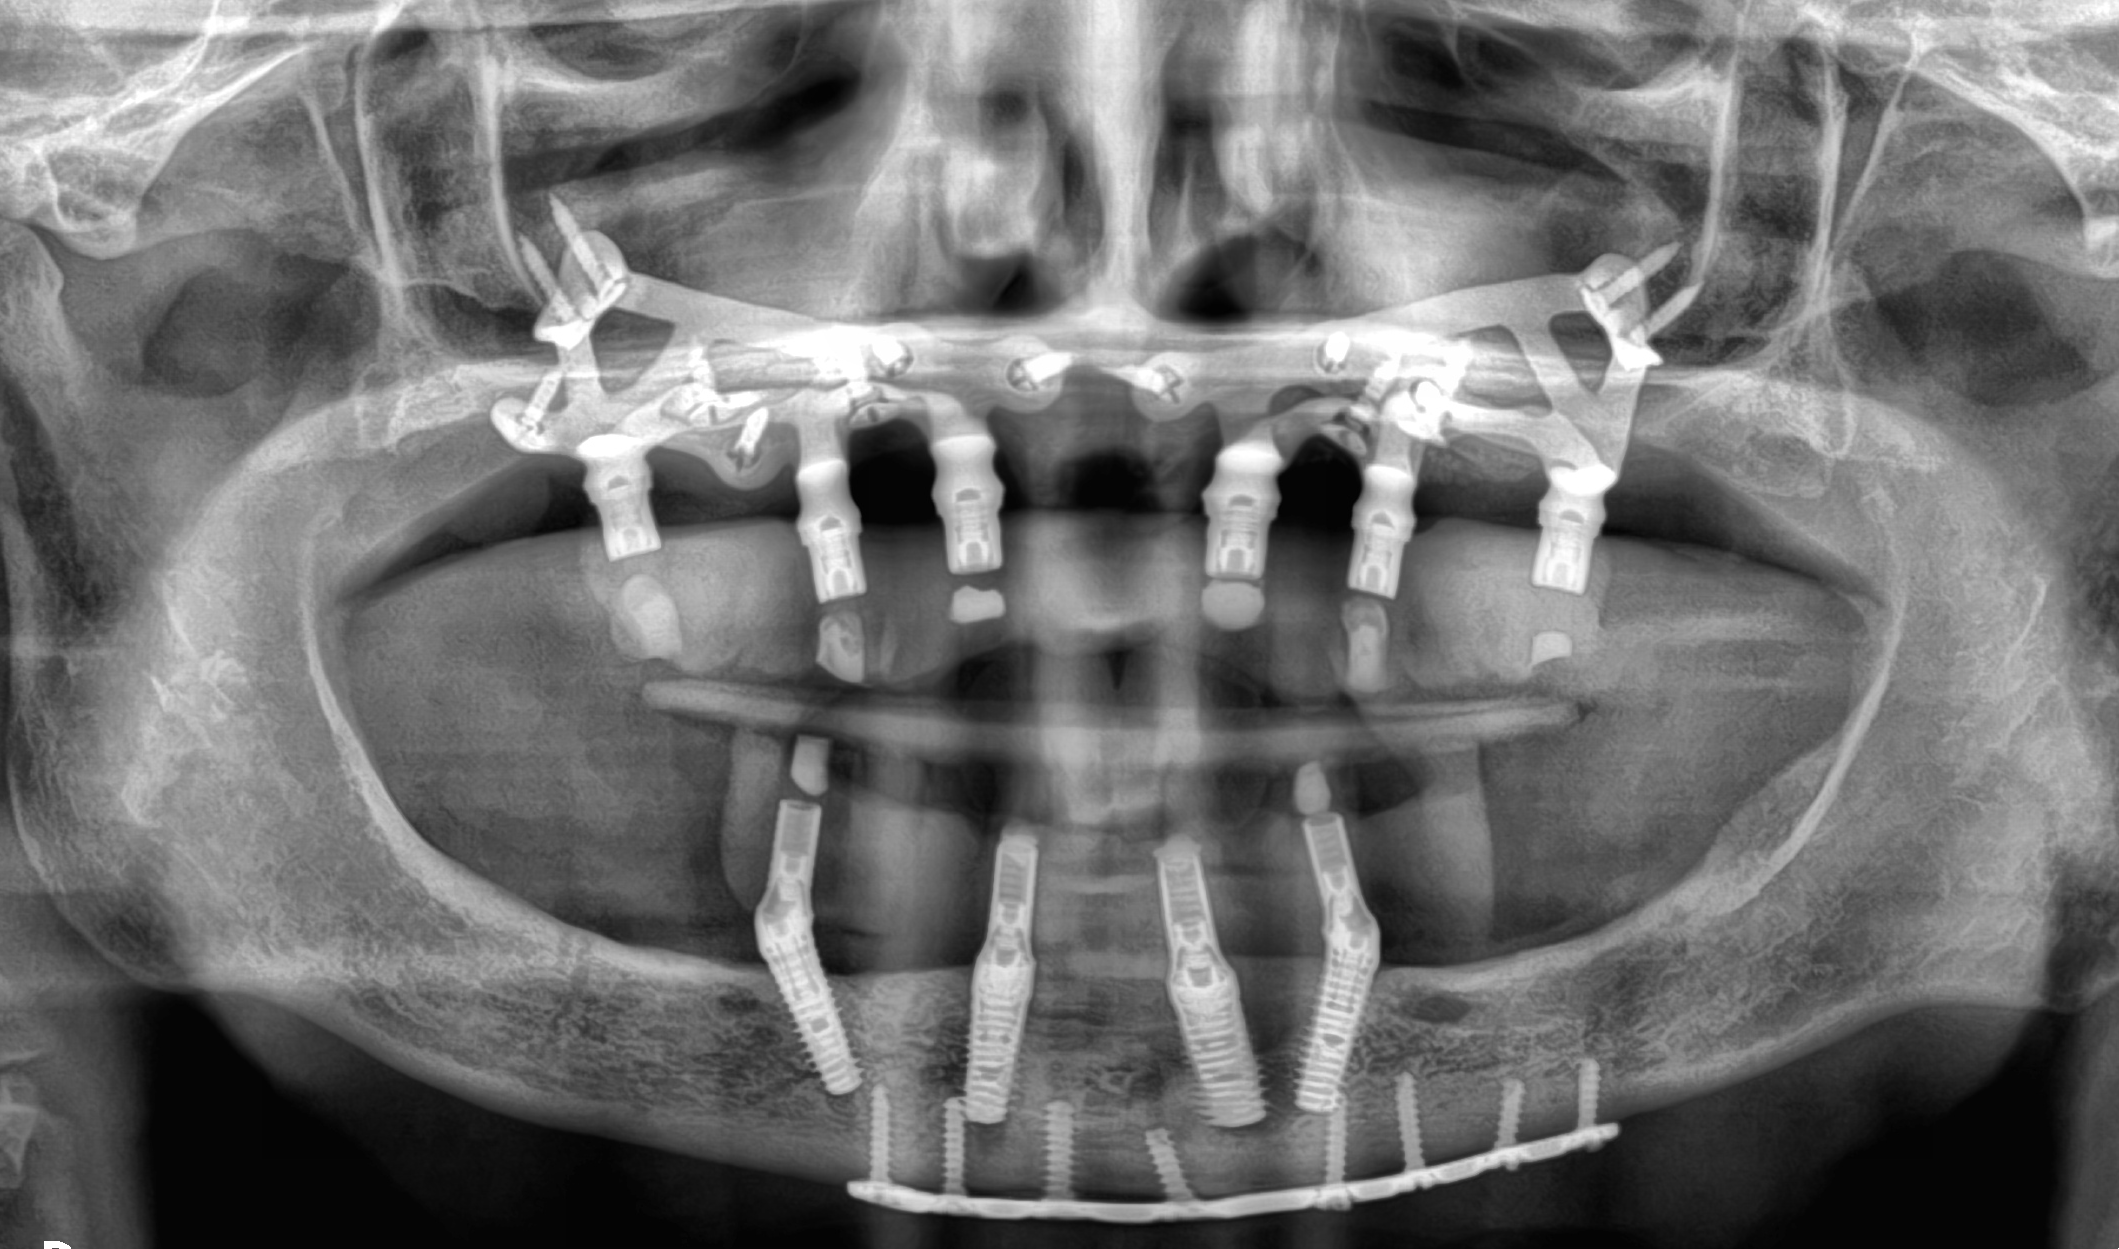

Riabilitazioni complete nei pazienti totalmente edentuli

Quando invece il paziente ha perso tutti i denti, progettiamo una riabilitazione completa supportata da impianti dentali. Grazie a tecniche avanzate e pianificazioni personalizzate, è possibile ripristinare estetica, funzione masticatoria e comfort attraverso soluzioni fisse stabilmente ancorate all’osso, restituendo un sorriso nuovo e sicuro anche nelle condizioni cliniche più complesse.

Caso 5

A causa di vari problemi di salute, la paziente si trova in una situazione di edentulia completa in entrambe le arcate. Le attuali protesi mobili sono per lei fonte di forte insicurezza a causa della loro mobilità. Nonostante la scarsità di osso mascellare e la presenza di viti di osteosintesi nella mandibola si procede con una riabilitazione fissa su entrambe le arcate combinando impianti tradizionali (mandibola) con impianti iuta-gengivali, nella mascella.

DOPO